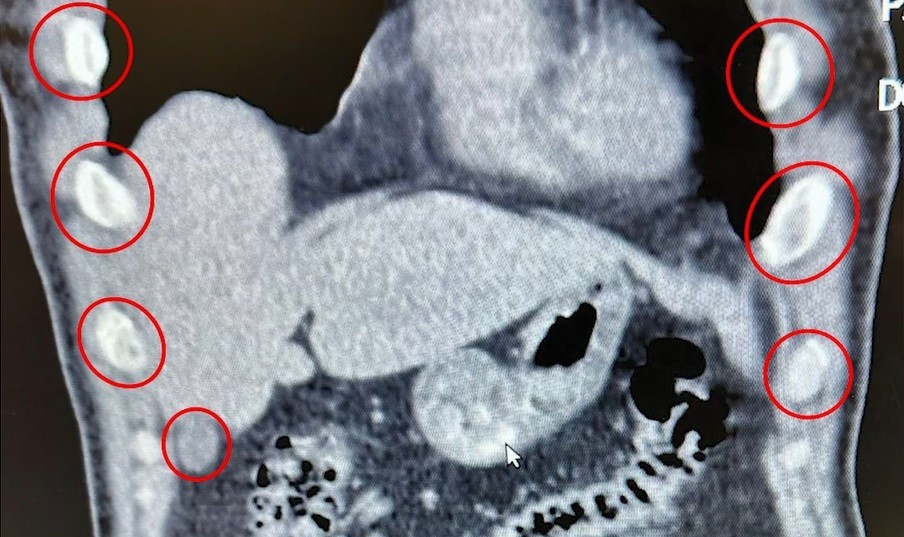

Bitlis'te düzenlenen narkotik operasyonunda yabancı uyruklu iki şüpheli, midelerinde taşıdıkları 136 uyuşturucu kapsülleriyle yakalandı.Bitlis İl Emniyet Müdürlüğü Narkotik Suçlarla Mücadele Şube Müdürlüğü ekipleri, uyuşturucu ile mücadele kapsamında önemli bir operasyona imza attı. Tatvan ilçesinde durdurulan bir otobüste yolcu olarak seyahat eden yabancı uyruklu 2 kişi gözaltına alındı. Şahısların yapılan tıbbi müdahalesinde, yuttukları 136 kapsül halinde toplam 1 kilo 48 gram metamfetamin ele geçirildi.Uyuşturucu Madde İmal ve Ticareti suçundan gözaltına alınan zanlılar, çıkarıldıkları adli mercilerce tutuklanarak cezaevine gönderildi.Emniyet yetkilileri, vatandaşların huzur ve güvenliği için uyuşturucu madde imalatı, kaçakçılığı ve kullanımına karşı mücadelenin kararlılıkla sürdürüleceğini vurguladı.

Midelerinden 136 Kapsül Uyuşturucu Çıktı

Bitlis'te düzenlenen narkotik operasyonunda yabancı uyruklu iki şüpheli, midelerinde taşıdıkları 136 uyuşturucu kapsülleriyle yakalandı.